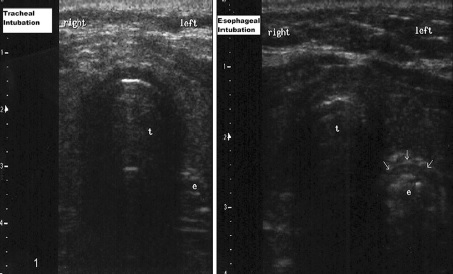

A confirmação do posicionamento correto do tubo endotraqueal é essencial para evitar situações de catástrofe em que a intubação esofágica ocorre e não é reconhecida, levando a sérios comprometimentos neurológicos e até a morte. O Advanced Cardiac Life Support (ACLS) indica o uso da capnografia como padrão ouro de checagem, porém, sabemos que há algumas limitações fisiológicas e alguns casos de resultados falsos negativos com este método. O uso do ultrassom transtraqueal surgiu como uma técnica não invasiva e segura para a visualização do posicionamento do tubo, em casos onde a capnografia não está disponível ou com uso comprometido, ou como adjunto do mesmo.

O ultrassom pode ser feito posicionando um transdutor linear ou convexo na topografia da membrana cricotireoidea ou na região da fúrcula esternal, na orientação transversa ou horizontal. A técnica pode ser feita durante a intubação ou após seu término. A visualização do ‘’sinal da tempestade de neve” (snowstorm) ou “sinal da bala” (bullet sign), com o achado de cauda de cometa ou de interface mucosa-aérea com sombra acústica posterior, confirma o correto posicionamento do tubo no interior da traqueia, tendo em vista que o próprio tubo não pode ser visualizado. Se visualizarmos uma dupla interface mucosa-aérea, com sombra acústica posterior, indica intubação esofágica, com a visualização do espaço paratraqueal à esquerda deste.

Imagem retirada de: Saurabh Kumar Das, MD • Nang Sujali Choupoo, MD • Rudrashish Haldar, MD • Amitabh Lahkar, MD Transtracheal ultrasound for verification of endotracheal tube placement: a systematic review and meta-analysis. Can J Anesth/J Can Anesth (2015) 62:413–423